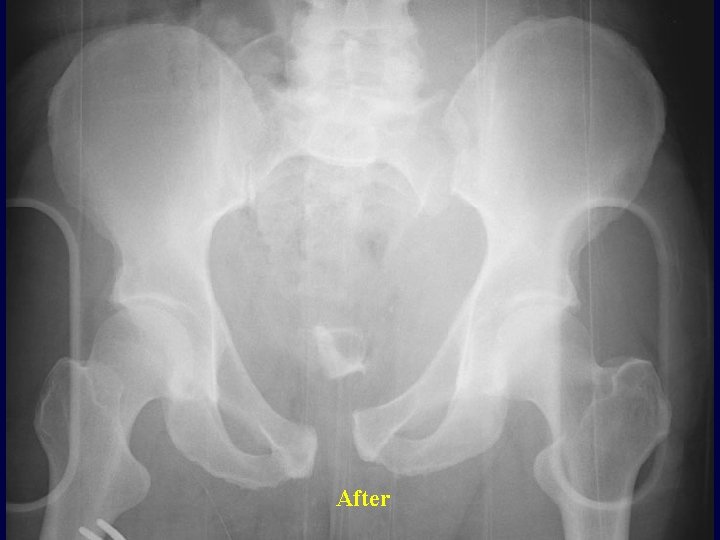

Sheet Application Before

After